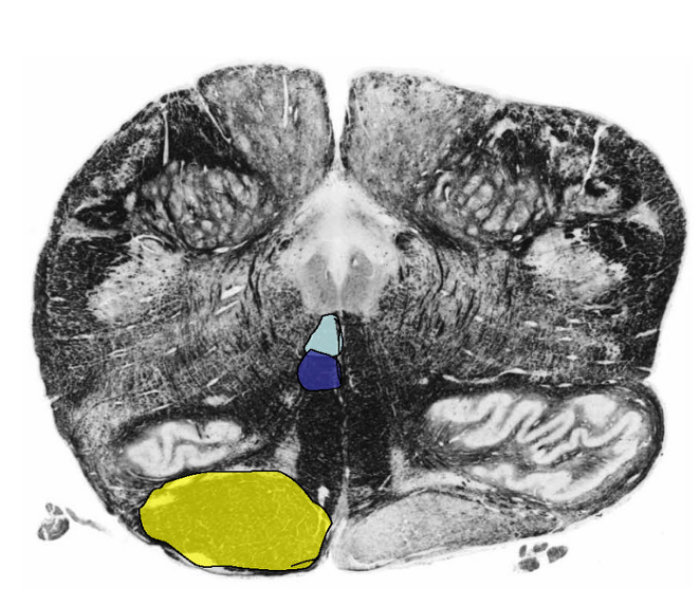

Describe the Pyramidal (Motor) Decussation

Location

Fiber Destiy

Somatotopy of Decussation

Location:

ventral surface of the medulla; disruption of the anterior median fissure

Fibers Destiny Here:

80-90 percent of corticospinal tract fibers decussates (L CST)

8% descend ipsilaterally → anterior funiculus → decussate segmentally (Anterior CST)

2% descend ipsilaterally to contribute to the lateral corticospinal tract (tract of Barnes)

Somatotopy of Decussation:

Upper Extremity fibers: Rostrally

Lower Extremity fibers: Caudally

THUS: iscrete lesions in the pyramidal decussation may produce different and somewhat unusual patterns of weakness.

What happens @ the level of Pyramidal Decussation (2) (besides CST decussation)

@ Level Pyramidal Decussation:

Fibers within fasciculus gracilis + fasciculus cuneatus synapse @ Nucleus Gracilis and nucleus cuneatus, respectively.

spinal trigeminal nucleus (pars caudalis) + tract take place of gray matter of dorsal horn and tract of Lissauer, respectively.